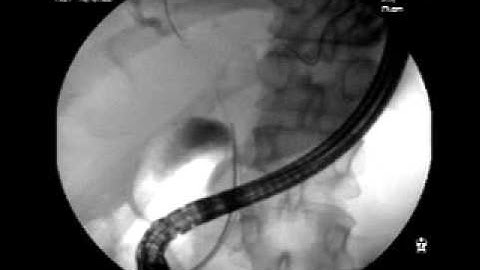

Proximal Cholangiocarcinoma